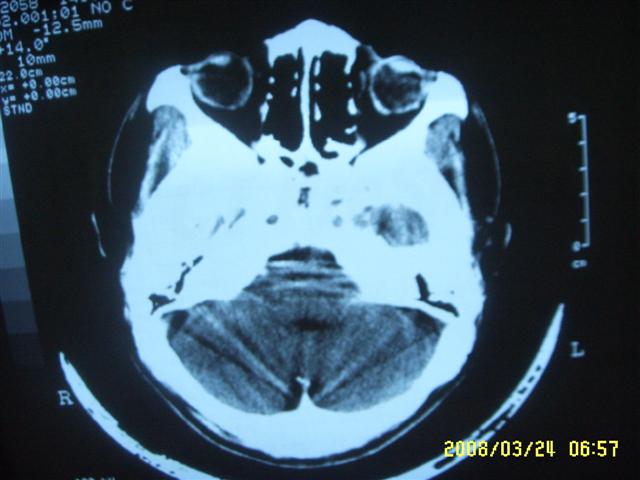

以下是引用dyqct在2008-4-2 20:09:00的发言:[br]考虑为:神经纤维瘤病(nf1型)。建议增强进一步检查。